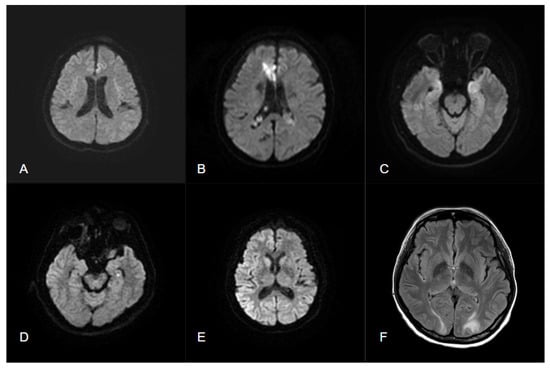

4.3. SRMA

4.3.5. SE

- Mariajoseph, F.P.; Sagar, P.; Muthusamy, S.; Amukotuwa, S.; Seneviratne, U. Seizure-induced reversible MRI abnormalities in status epilepticus: A systematic review. Seizure 2021, 92, 166–173. [Google Scholar] [CrossRef] [PubMed]

- Huang, Y.C.; Weng, H.H.; Tsai, Y.T.; Huang, Y.C.; Hsiao, M.C.; Wu, C.Y.; Lin, Y.H.; Hsu, H.L.; Lee, J.D. Periictal magnetic resonance imaging in status epilepticus. Epilepsy Res. 2009, 86, 72–81. [Google Scholar] [CrossRef]

- Chatzikonstantinou, A.; Gass, A.; Förster, A.; Hennerici, M.G.; Szabo, K. Features of acute DWI abnormalities related to status epilepticus. Epilepsy Res. 2011, 97, 45–51. [Google Scholar] [CrossRef]

- Requena, M.; Sarria, E.S.; Santamarina, E.; Quintana, M.; Sueiras, M.; Rovira, A.; Toledo, M. Peri-ictal magnetic resonance imaging in status epilepticus: Temporal relationship and prognostic value in 60 patients. Seizure 2019, 71, 289–294. [Google Scholar] [CrossRef]